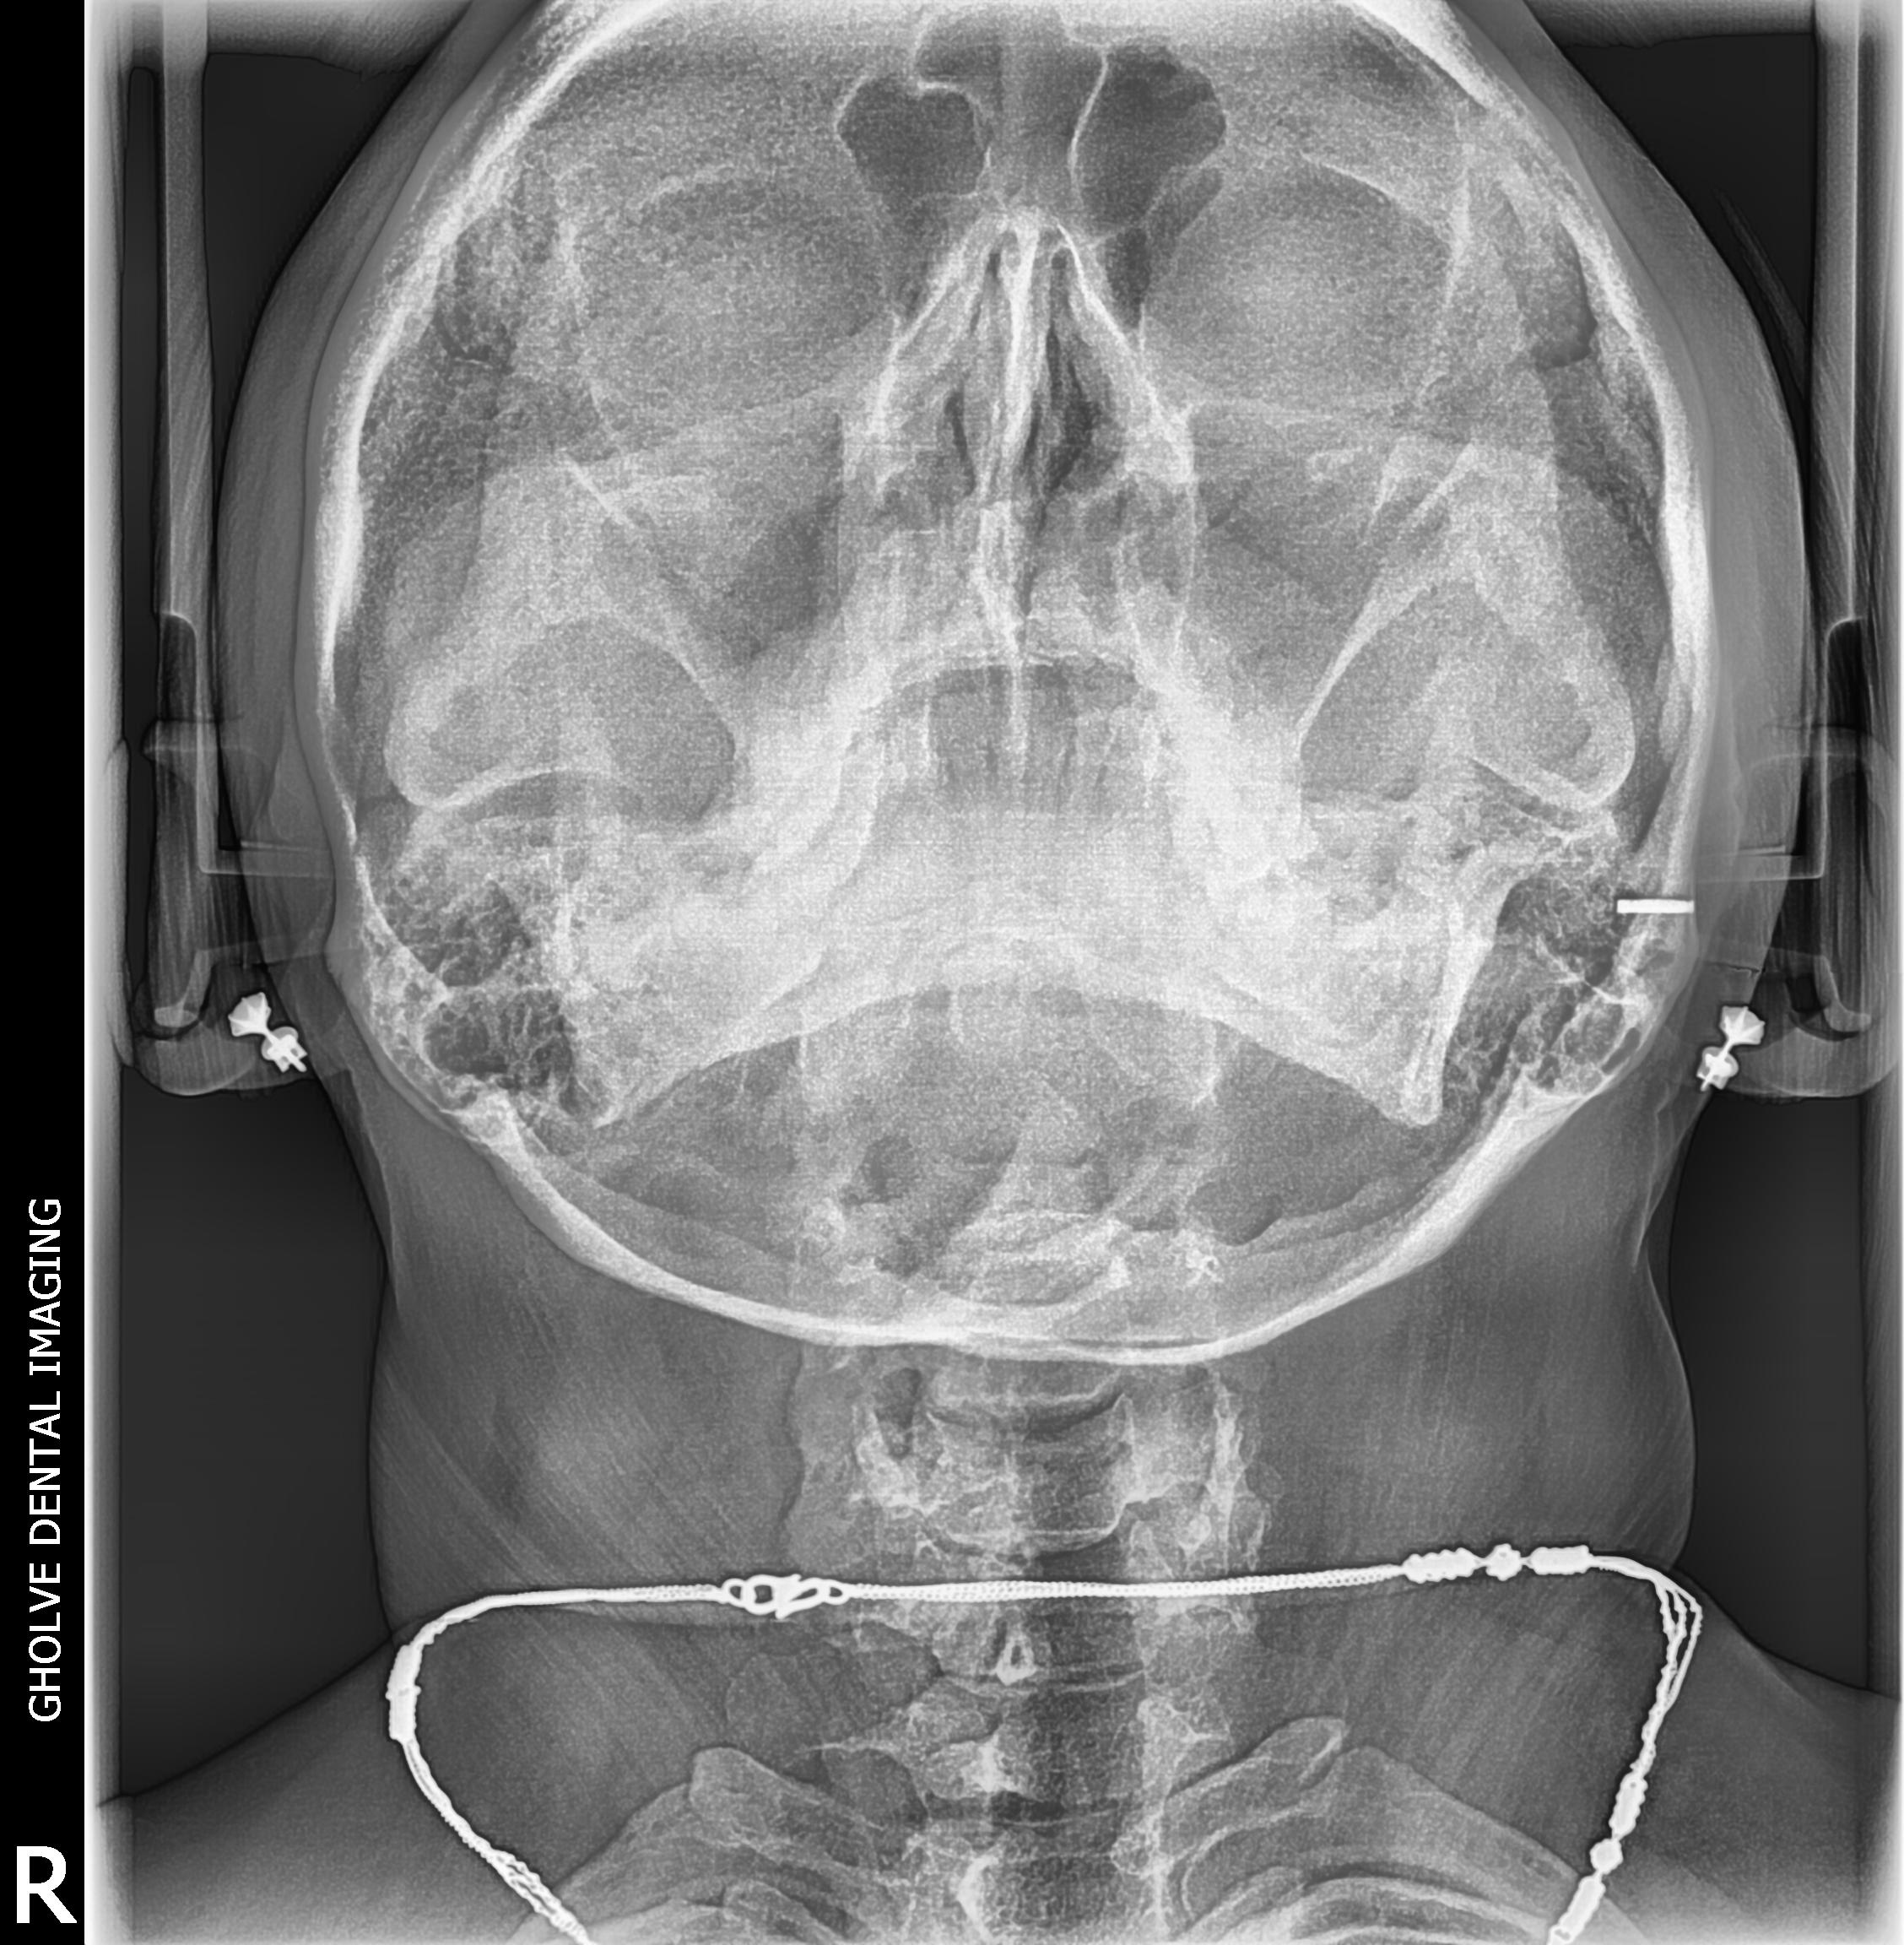

X Ray Of Pns Waters View . paranasal sinuses and facial bones radiography is the radiological investigation of the facial bones and paranasal sinuses. To capture the most detailed and informative images of the sinuses, radiologists utilize various viewing. occipitofrontal view (caldwell view) occipitomental (om) or waters view. waters view (also known as the occipitomental view) helps to get a better view of the maxillary sinuses by using x. paranasal sinuses radigraphy pns x rays waters view. Normal mucosa of the paranasal sinuses appear. Lateral view, caldwell’s view, waters’ view, and submentovertex or base. the standard radiographic sinus series consists of four views:

Normal mucosa of the paranasal sinuses appear. waters view (also known as the occipitomental view) helps to get a better view of the maxillary sinuses by using x. Lateral view, caldwell’s view, waters’ view, and submentovertex or base. paranasal sinuses radigraphy pns x rays waters view. To capture the most detailed and informative images of the sinuses, radiologists utilize various viewing. paranasal sinuses and facial bones radiography is the radiological investigation of the facial bones and paranasal sinuses. occipitofrontal view (caldwell view) occipitomental (om) or waters view. the standard radiographic sinus series consists of four views: